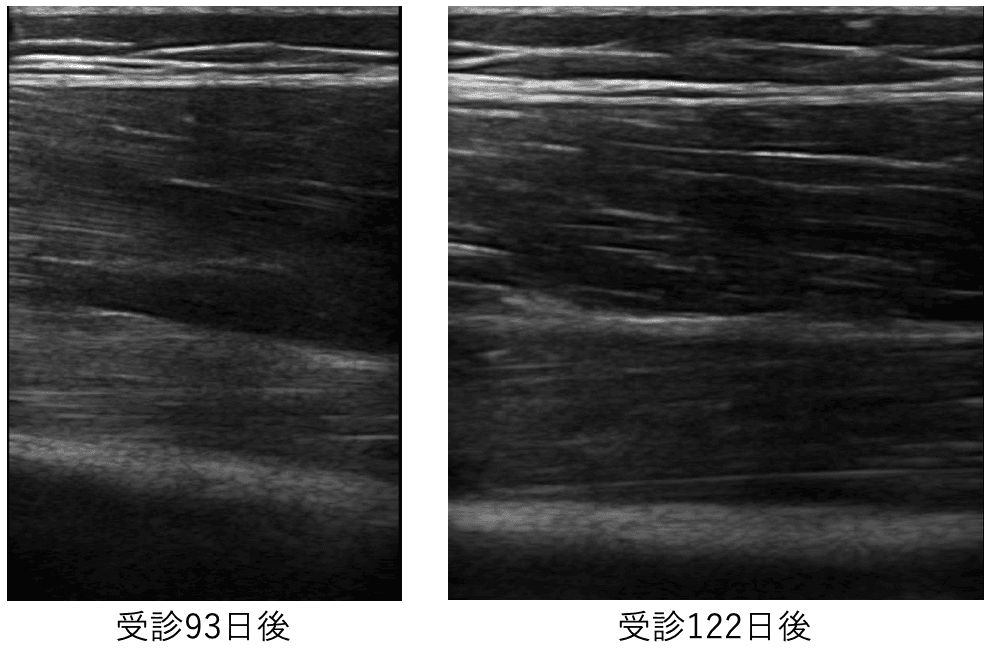

当院受診93日後から122日後までのエコー画像です。

完璧に石灰像は吸収され、治療終了としました。